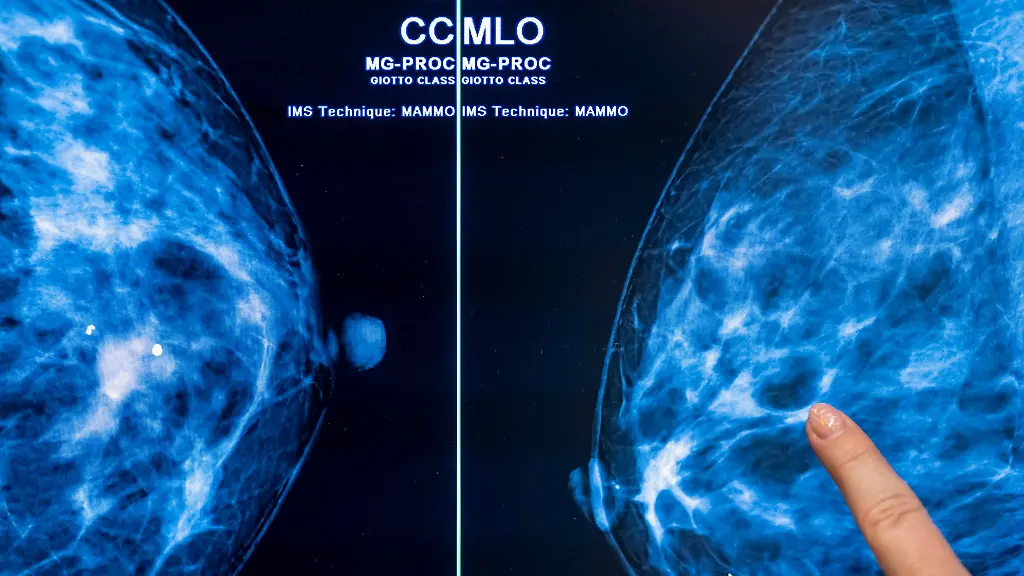

Eine Krebsdiagnose trifft die Betroffenen oft wie ein Schlag und völlig unerwartet. Beim Brustkrebs steigen die Zahlen in Niedersachsen deutlich - und nicht nur dort.

Hannover (dpa/lni) - In Niedersachsen sind nach Daten der Kaufmännischen Krankenkasse KKH binnen zehn Jahren deutlich mehr Frauen an Brustkrebs erkrankt. Demnach seien 2023 landesweit 39,1 Prozent mehr Frauen wegen einer Brustkrebs-Diagnose in Behandlung gewesen als zehn Jahre zuvor, teilte die KKH mit. Landesweit stieg der Anteil der Brustkrebs-Patientinnen am Versichertenbestand zwischen 2013 und 2023 von 2,6 Prozent auf rund 3,7 Prozent. Insgesamt gebe es 1.725 Betroffene in Niedersachsen, sagte eine Sprecherin.

Bösartige Veränderungen des Brustgewebes sind den Angaben zufolge die häufigste Krebserkrankung bei Frauen. Die KKH zählt nach eigenen Angaben mit rund 1,5 Millionen Versicherten zu den größten bundesweiten Krankenkassen.

"Die Diagnose Krebs trifft die meisten Patientinnen völlig unerwartet", sagte Aurelia Tegtmeyer, Ärztin bei der KKH. Neben genetischer Veranlagung und Alter könnten auch Ernährung und Bewegung eine Rolle bei der Entstehung von Brustkrebs spielen. "Nicht alle Risikofaktoren für Brustkrebs sind beeinflussbar, allen voran das Alter und eine familiäre Vorbelastung", sagte die Medizinerin. Werde Brustkrebs in einem frühen Stadium erkannt, sei er meistens gut behandelbar - und die Aussicht auf Heilung am größten.